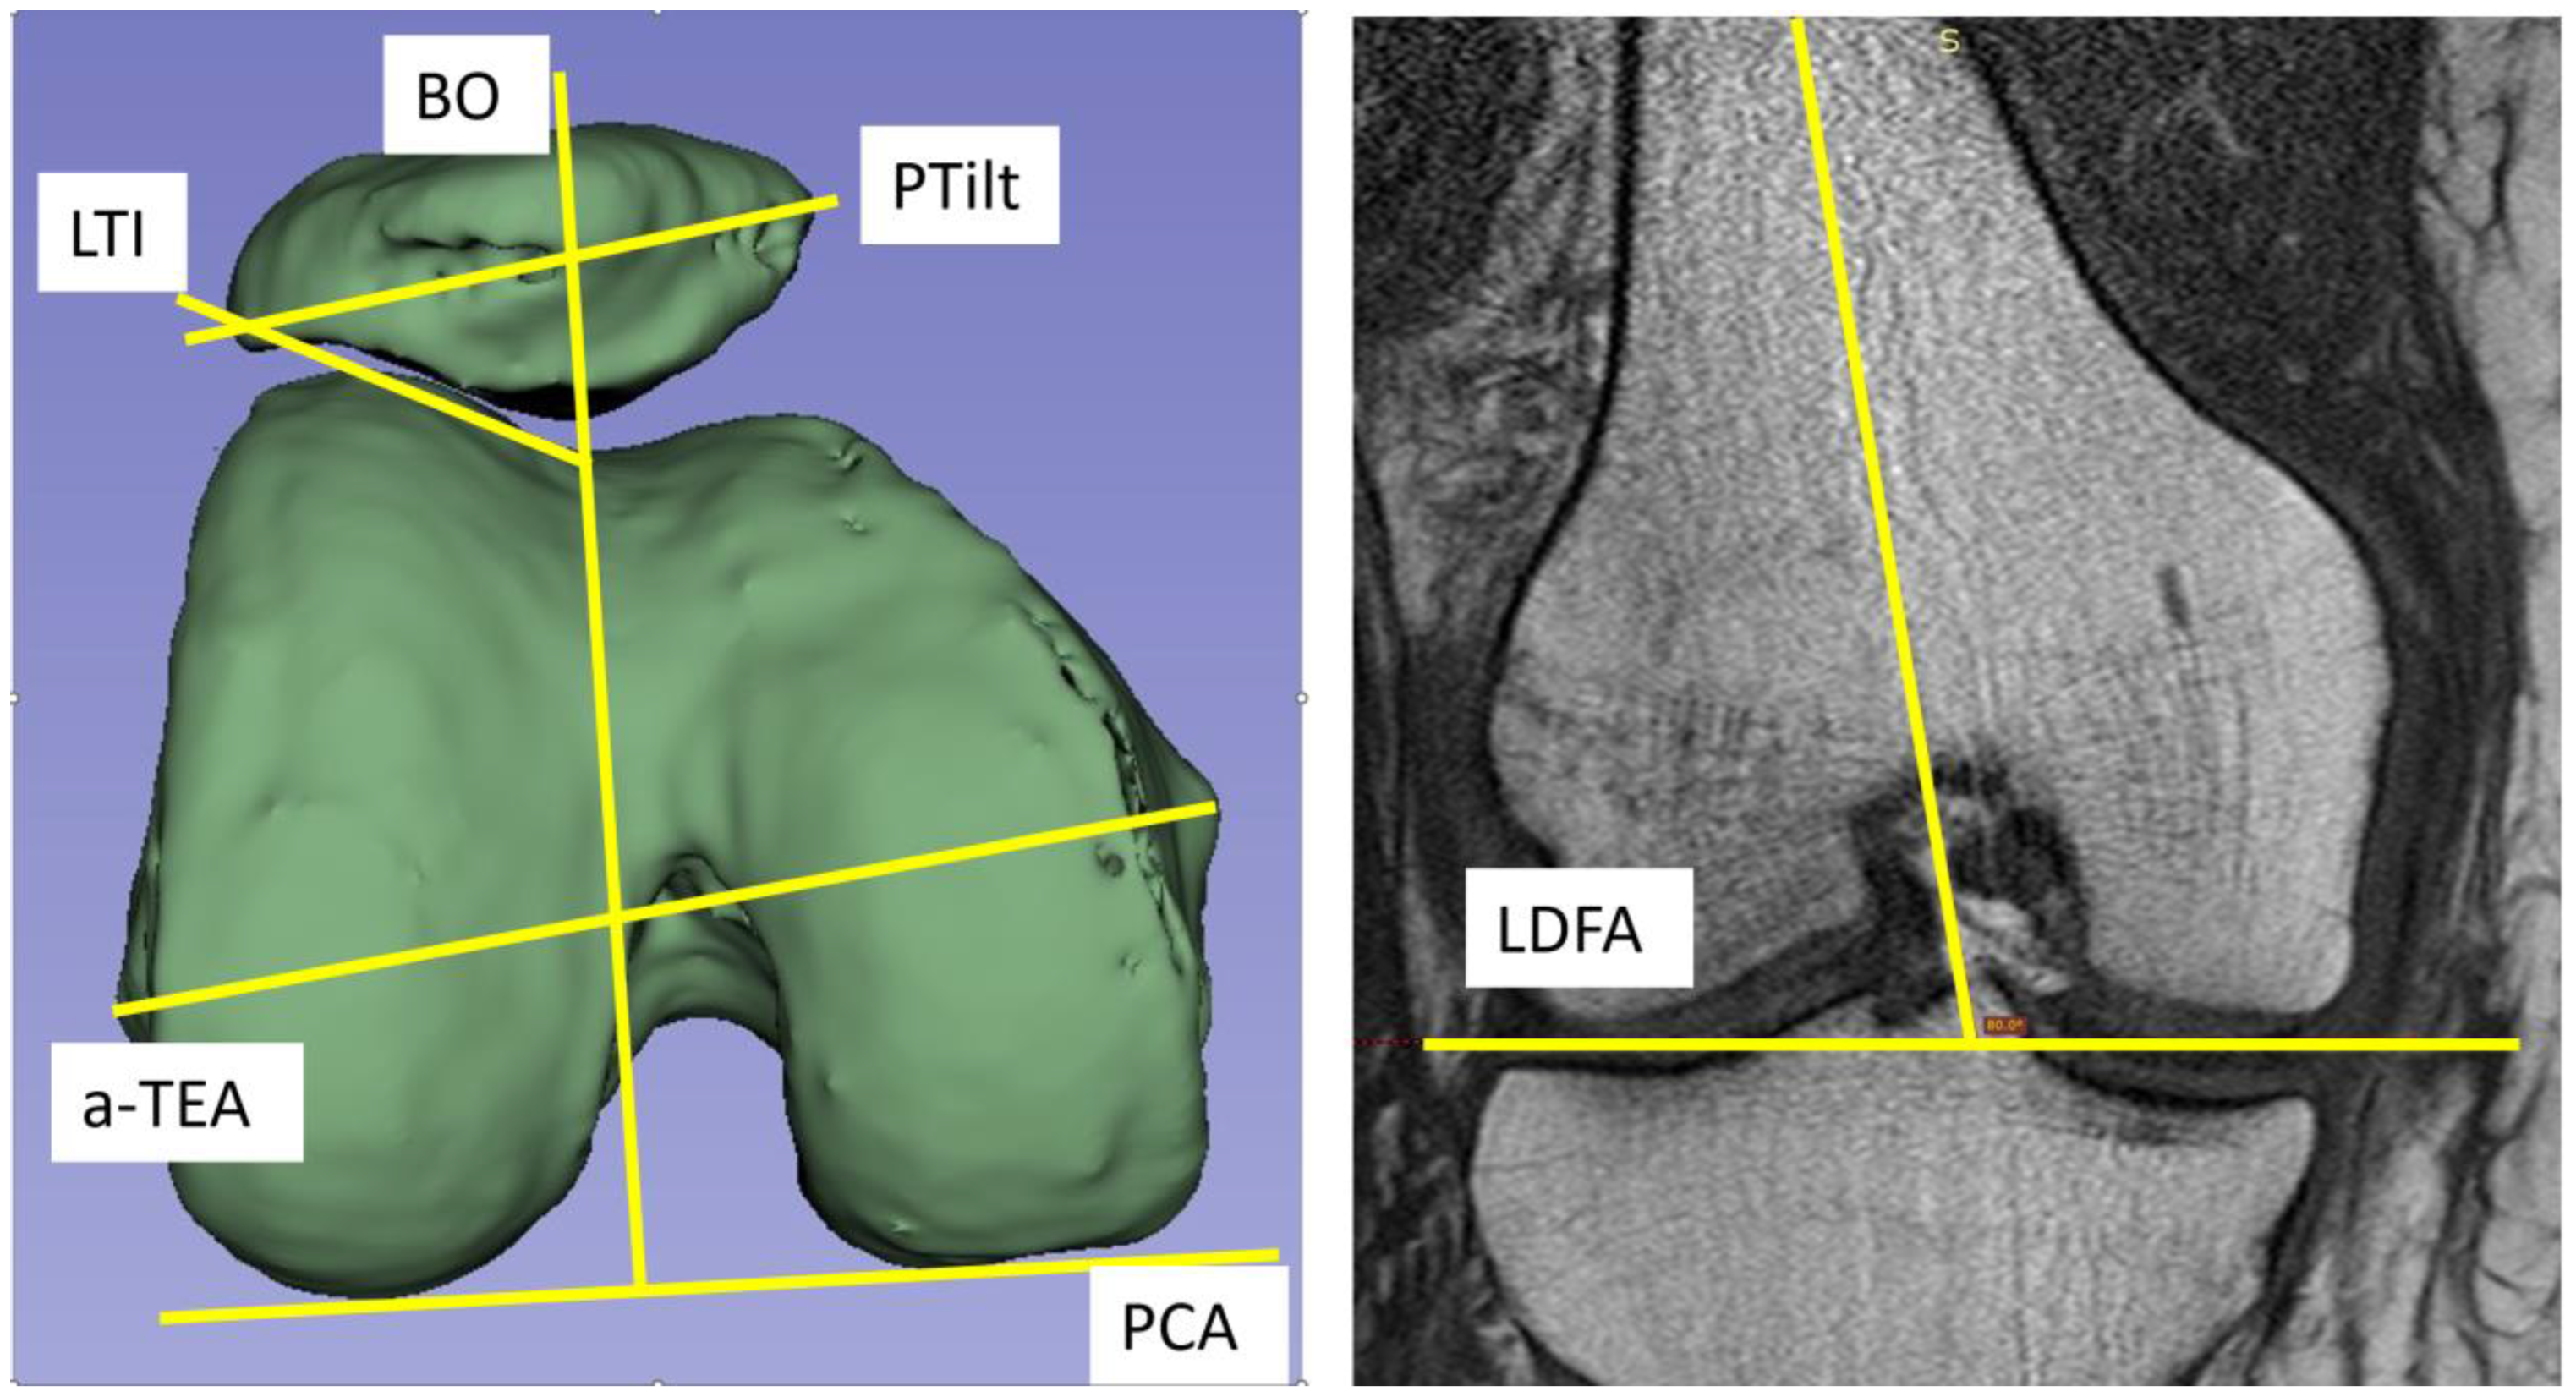

| LDFA | Lateral distal condylar angle |

| Variable | N | Average | Std-Dev. | Min | Max | LDFA | PCA | ||||

|---|---|---|---|---|---|---|---|---|---|---|---|

| LDFA [°] | 94 | 82.35 | 1.81 | 78.3 | 86.6 | Pearson correlation | two-side p-value | N | Pearson correlation | two-side p-value | N |

| PCA [°] | 100 | 6.49 | 2.02 | 2.4 | 10.6 | ||||||

| LTI [°] | 99 | 19.58 | 3.87 | 10 | 28 | 0.129 | 0.219 | 93 | −0.319 | 0.001 | 99 |

| PTilt [°] | 94 | 10.31 | 4.04 | 1 | 18 | −0.100 | 0.350 | 89 | 0.428 | <0.001 | 94 |

| BO [%] | 94 | 58.20 | 6.00 | 45.6 | 73.8 | 0.013 | 0.902 | 88 | 0.330 | 0.001 | 94 |